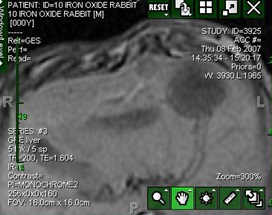

MRI检出率两组均为100%,较小粒径的顺磁性微粒100~300μm,IOE在肿瘤内检出率为30%,病例分析,IOE肿瘤内检出率为70%,大粒径300~500μm,组织学分析和MRI显示在肝动脉内的肿瘤外。

含氧化铁的微粒经肝动脉栓塞后在肝癌动物模型中的分布:使用MRI评价。

理想的药物释放: Importance of Particle Size:动脉栓塞治疗Vx-2肝脏肿瘤:含氧化铁微粒 300~500 μm 与100-300μm 比较